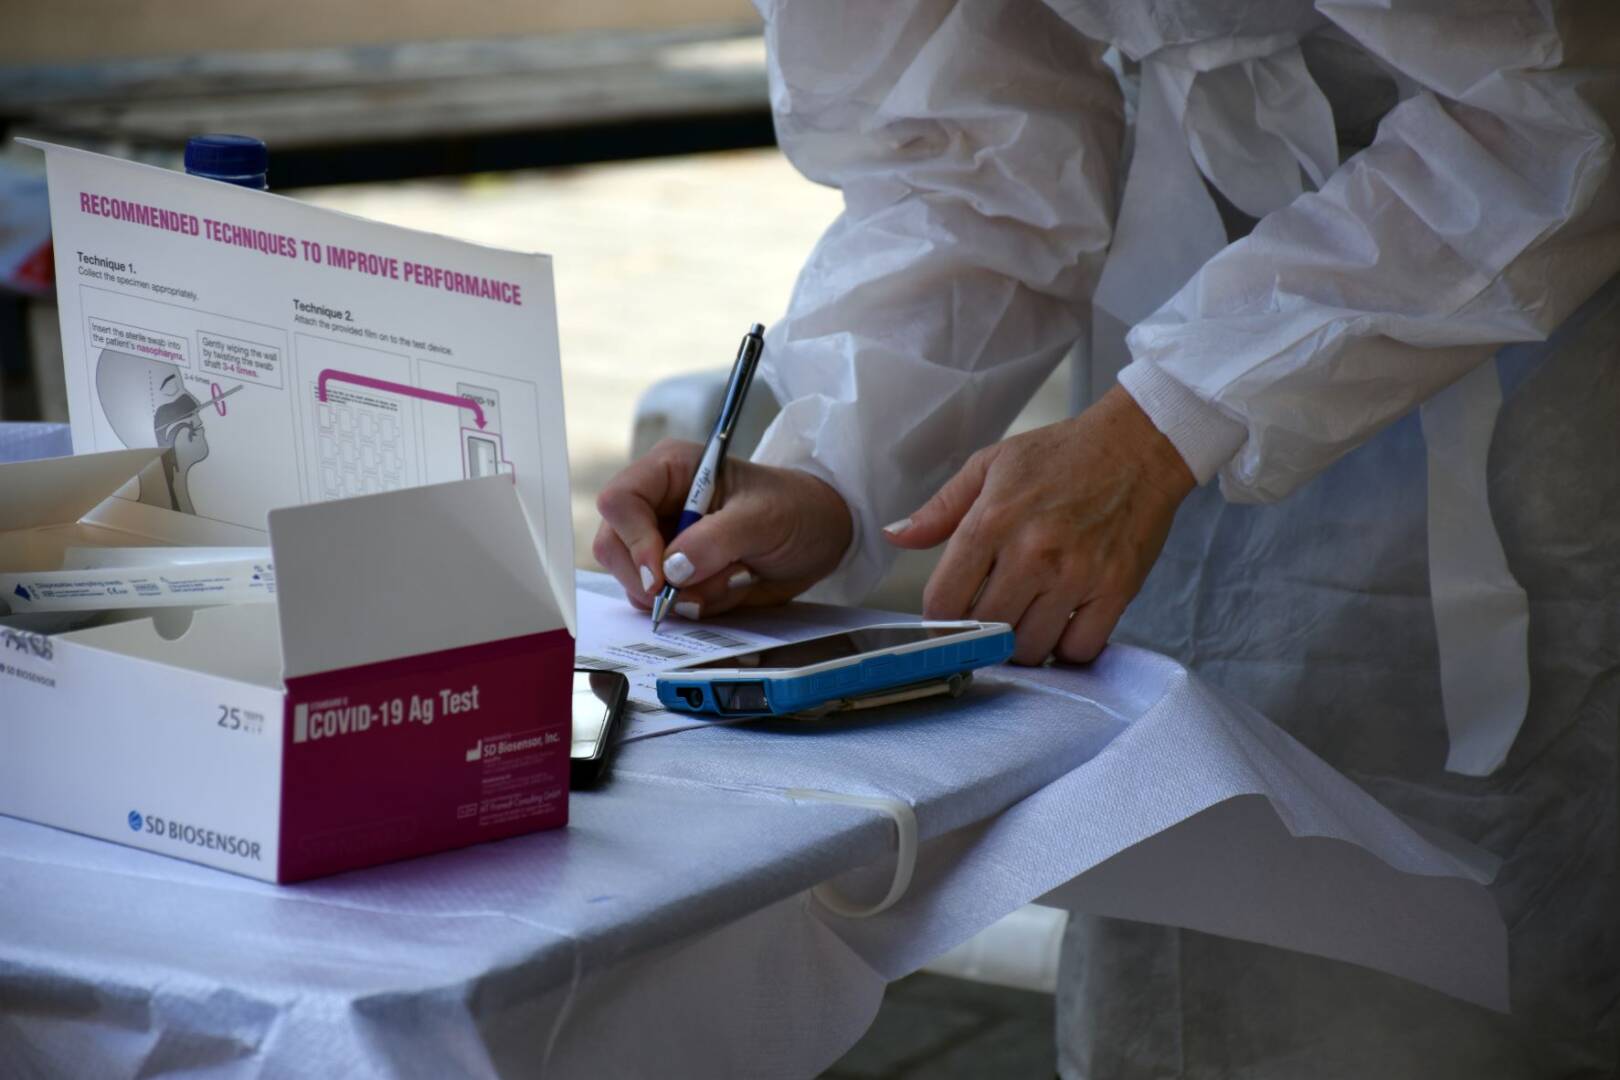

Τεστ αίματος αυτο-αντισωμάτων μπορεί να προβλέψει την πιθανότητα σοβαρής Covid-19

Η παρουσία συγκεκριμένων αυτο-αντισωμάτων στο αίμα των νοσηλευόμενων ασθενών με Covid-19, σχετίζεται στενά με τον κίνδυνο να νοσήσουν βαριά, σύμφωνα με μια νέα αμερικανική επιστημονική έρευνα. Τα αυτο-αντισώματα στον οργανισμό είναι πρωτεΐνες που, αντί να αμύνονται έναντι των βακτηρίων και των ιών, επιτίθενται στα ίδια τα κύτταρα και τα μόρια του ασθενούς. Ένα νέο απλό […]

ΕΜΑ: Ενδεχομένως ανησυχητική η παραλλαγή Μι

Η παραλλαγή Μι, που ταυτοποιήθηκε για πρώτη φορά στην Κολομβία τον Ιανουάριο, είναι «ενδεχομένως ανησυχητική», αλλά δεν υπάρχουν ακόμη δεδομένα που να δείχνουν ότι μπορεί να ξεπεράσει την παραλλαγή Δέλτα ως κυρίαρχο στέλεχος, δήλωσε σήμερα η ευρωπαϊκή ρυθμιστική αρχή. Η παραλλαγή B.1.621, σύμφωνα με την επιστημονική ονοματολογία, ταξινομήθηκε ως «παραλλαγή υπό παρακολούθηση» από τον Παγκόσμιο […]

Πόσο εφικτό είναι να κολλήσει κανείς κοροναϊό σε δημόσια τουαλέτα

Μια νέα επιστημονική μελέτη, με επικεφαλής έναν Έλληνα επιστήμονα της διασποράς, δεν βρήκε καμία ένδειξη για αερογενή μετάδοση της Covid-19 μέσα στις δημόσιες τουαλέτες, ενώ ως μικρή αξιολογεί και την πιθανότητα μόλυνσης από επιφάνειες, εφόσον τηρούνται τα αναγκαία μέτρα υγιεινής. Οι ερευνητές, με επικεφαλής τον καθηγητή περιβαλλοντικής υγείας Σωτήρη Βαρδουλάκη του Αυστραλιανού Εθνικού Πανεπιστημίου, οι […]